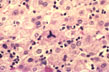

Fig. 133 - Infectious mononucleosis hepatitis

Marked mononuclear cell infiltration of the sinusoids without significant necrosis. H&E stain.